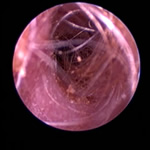

耳ダニ感染後の鼓膜喪失と中耳炎

長く耳ダニに気付かず治療が遅れた猫です。すでに鼓膜を失っており、中耳をきれいに洗浄すると赤い肉芽が確認できました。この肉芽を除去し点耳薬で治療すると改善。鼓膜が全く残っていないため鼓膜の再生は期待できませんが、痛みや痒みもなく元気に過ごしています。